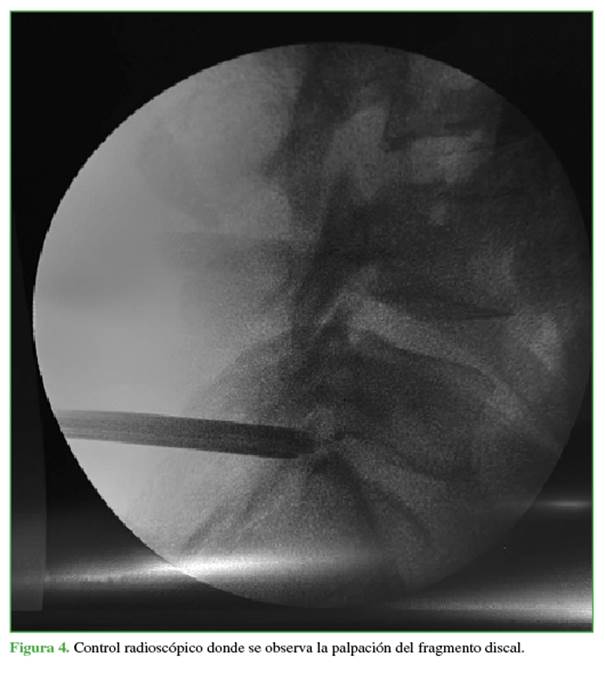

Mediante la introducción de un gancho separador, se palpa el fragmento discal extruido en el espacio extrafo-raminal (Figura 4). Se procede a la exéresis del fragmento extruido con la pinza fórceps de disco (Figura 5) y se verifica la correcta liberación de la raíz de L5 (Figura 6 y Video).